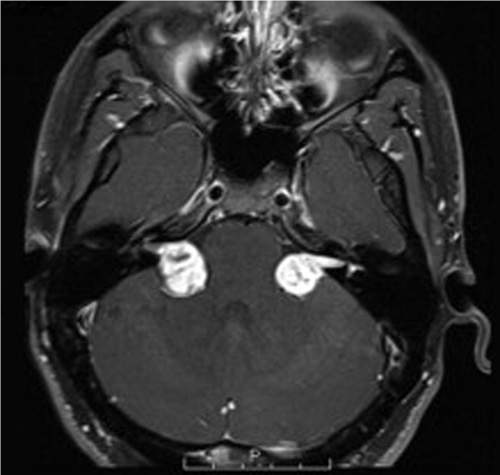

A 36-year-old man presents with a 1-year history of gradual bilateral hearing loss, a sense of aural fullness, and progressively impaired balance. He has a history of juvenile cataracts, and his brother and father have similar difficulties with their hearing. A brain magneticresonance image (MRI) with contrast is shown. Which of the following is the most likely cause of his symptoms?

Taking into account the patients medical and family history, as well as the MRI, the most likely cause of his hearing difficulties is bilateral vestibular schwannomas. These are noted to have bright, fairly homogeneous enhancement, as well as the classical ice cream cone shape on MRI, with the cone represented by the enhancing portion of the tumor entering the internal auditory canal. Medulloblastoma is a tumor of the posterior fossa, generally involving the cerebellum, but is not bilateral or homogeneously enhancing. Therefore involvement of the internal auditory canals is not easily explained by this diagnosis. Leptomeningeal metastasis does often affect cranial nerves, such as the acoustic nerves, but would be rare to present so slowly or with such large tumor burden on MRI. Further, there is no leptomeningeal enhancement on MRI. Glioblastoma is exceedingly rare in the posterior fossa, and would not explain the internal auditory canal involvement or the enhancement homogeneity. Meningiomas are a reasonable consideration given the radiographic appearance, but the specific internal auditory canal involvement and lack of dural tail point away from this diagnosis. Also the positive family history suggests only vestibular schwannomas out of the available choices